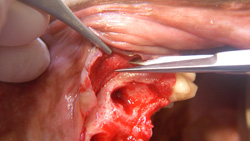

Complications